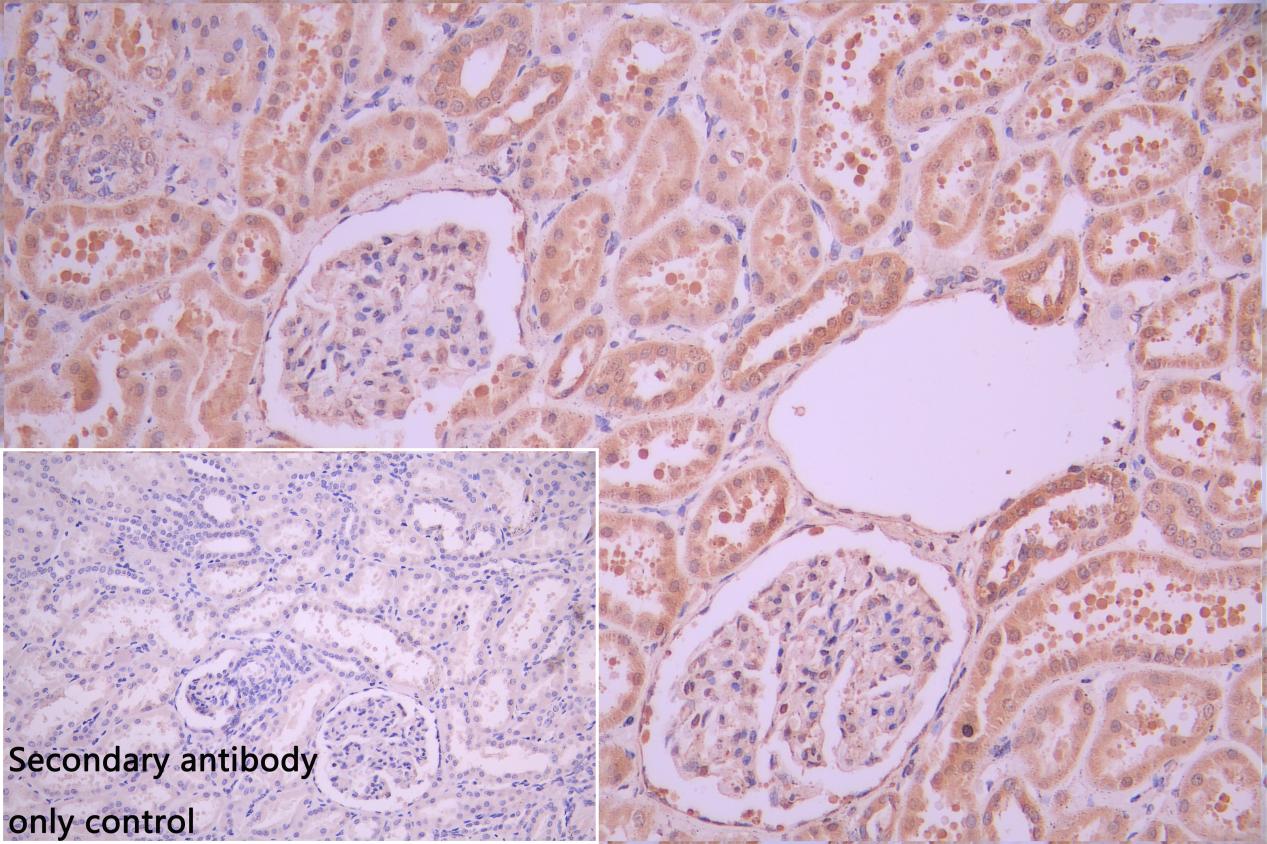

IHC image of CSB-PA896505DSR2HU diluted at 1:50 and staining in paraffin-embedded human kidney tissue performed on a Leica BondTM system. After dewaxing and hydration, antigen retrieval was mediated by high pressure in a citrate buffer (pH 6.0). Section was blocked with 10% normal goat serum 30min at RT. Then primary antibody (1% BSA) was incubated at 4°C overnight. The primary is detected by a Goat anti-rabbit polymer IgG labeled by HRP and visualized using 0.05% DAB. Secondary antibody only control: uses 1% BSA instead of primary antibody